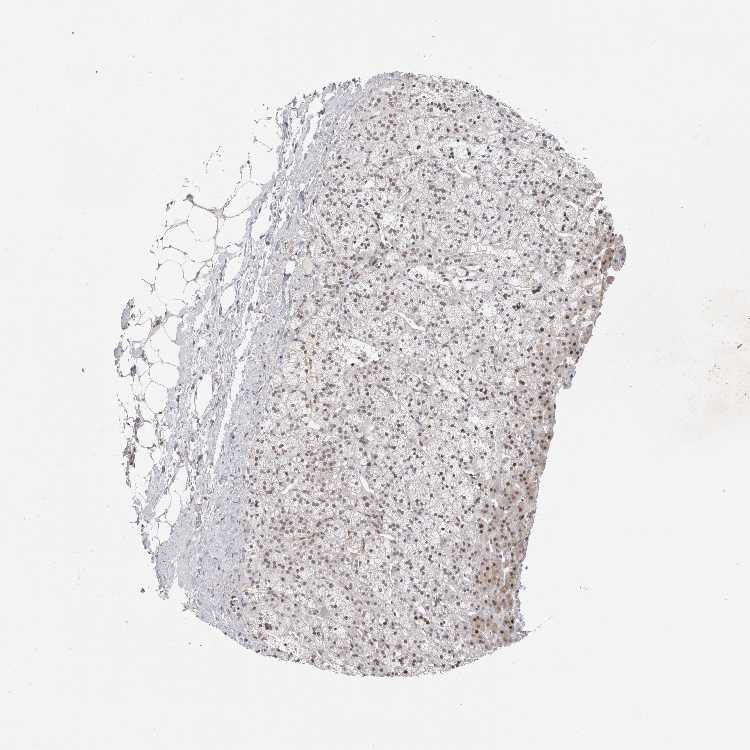

ADRENAL GLAND - Antibody stainingi

Antibody staining in the annotated cell types in the current human tissue is reported as not detected, low, medium, or high, based on conventional immunohistochemistry profiling in selected tissues. This score is based on the combination of the staining intensity and fraction of stained cells.

Each image is clickable and will lead to virtual microscopy that enables deeper exploration of all samples and also displays staining intensity scores, fraction scores and subcellular localization as well as patient and tissue information for each sample.

Antibody HPA026676

Glandular cells Medium